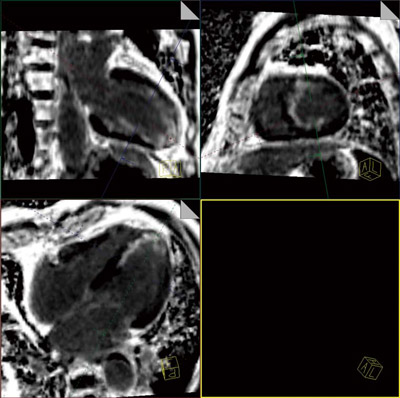

最近では,Navigatorを併用した自由呼吸下での高空間分解能の3D遅延造影撮像が一般的に行われるようになってきており,遅延造影領域の連続性や広がり診断に有用であると報告されている。一方で,造影剤注入後の正常心筋の至適TI値は,血中の造影剤濃度の時間変化に依存し,遅延造影画像の撮像中に刻一刻と変化していく。そのため,呼吸同期による3D遅延造影撮像では,被検者の呼吸状態によりデータ収集に必要な撮像時間が推測しづらく,至適TI値の設定が困難であるという問題点を有する(図3)。しかし,3D Phase Sensitive IR法を用いることにより,この至適TI値の問題を解決することが可能である。これにより,被検者に呼吸状態やTI値の設定条件にかかわらず,最適なコントラストの高空間分解能の3D遅延造影画像を取得することができる(図4)。

図4 3D Phase Sensitive IR法による高空間分解能3D遅延造影画像